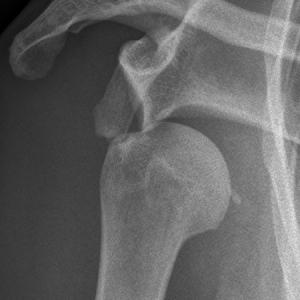

Hüfte

Nach dem Kniegelenk ist das Hüftgelenk das zweitgrösste Gelenk des Menschen. Als so genanntes Nussgelenk, eine Form des Kugelgelenkes, wird es vom Kopf des Oberschenkelknochens und der Pfanne im Becken gebildet. Unterstützt wird es durch eine Vielzahl von muskulären und bandhaften Strukturen und Weichteilen, die eine optimale Zentrierung des Gelenkes ermöglichen. Häufige Ursachen von Beschwerden (Hüftschmerzen) sind Gelenkverschleiss (Arthrose), Verletzungsfolgen, rheumatisch-entzündliche Erkrankungen und Durchblutungsstörungen. Ebenfalls können angeborene Veränderungen der Gelenkspartner schmerzhaft werden. Weitere Ursachen sind Überbeanspruchung in Sport und Beruf.

Sowohl die Hüftgelenkspfanne als auch der Oberschenkelkopf sind mit Knorpel überzogen. Dieser gewährleistet eine reibungsarme Gleitfähigkeit gegeneinander. Im Verlauf des Lebens oder provoziert durch Unfälle kann es zu einem Verschleiß des Knorpels kommen. Dieser äußert sich in hüftnahen- und Leistenschmerzen, morgendlicher Steifigkeit im Gelenk sowie einem Belastungs- oder Anlaufschmerz. Im weiteren Verlauf können, durch die schmerzbedingte Veränderung des Gangbildes, Beschwerden in den angrenzenden Gelenken auftreten. Das Gelenk verändert sich und Knochenanlagerungen an den Rändern (Osteophyten) verursachen eine zusätzliche Bewegungseinschränkung sowie Abriebprodukte, welche zunehmend Schmerzen verursachen. Neben der eingeschränkten Beweglichkeit können die belastungsabhängigen Beschwerden zunehmen , bis hin zu ständigen, auch nächtlichen Schmerzen. Die Beschwerden müssen dabei nicht auf die Hüfte beschränkt sein, sondern können auch sowohl in die Leiste als auch in den hinteren Oberschenkel ausstrahlen. Je nach Stadium der Arthrose stehen verschiedene Behandlungsmöglichkeiten zur Verfügung, die von der nicht-operativen Therapie bis hin zum Ersatz des Hüftgelenk mit einem Kunstgelenk (Hüftprothese) reichen.

Operative Therapie

Wenn die Schmerzen durch eine konservative Therapie nicht mehr behandelt werden können und, die Lebensqualität sinkt, ist ein operatives Verfahren möglich. Hierzu gibt es künstliche Gelenke mit denen die geschädigten Gelenkoberflächen ersetzt werdem, die sogenannten Hüftendoprothesen. Nach exakter Planung, anhand von Röntgen- und ggf. auch MRI-Bildern, erfolgt die Festlegung des individuellen Modells und die Größe der neuen Gelenkpartner. Wenn immer möglich benutzen wir einen gewebeschonenden, minimalinvasiven Zugangsweg zum Hüftgelenk. Entgegen den früher durchgeführten Schnitten durchtrennen wir weder Muskeln noch lösen wir diese vom Knochen ab. Nach Einpassen der vorher geplanten und während der Operation kontrollierten neuen Gelenkpartner, werden diese meist zementfrei im Knochen verankert. Die Fixation wird je nach Knochenqualität, Alter und Prothesentyp gewählt. Daraus ergibt sich ein sehr geringes Gewebetrauma und es kann gewährleistet werden, dass bei jeder Operation die bestehende Anatomie berücksichtigt und eine optimale Funktion wiederhergestellt wird.